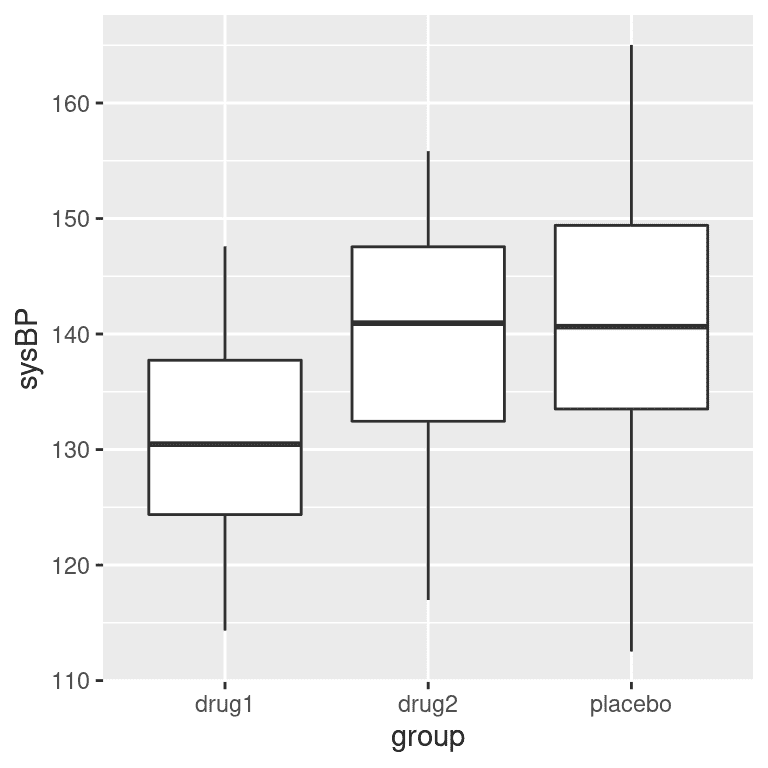

通常我们希望比较两个以上的均值,以确定它们是否彼此不同。假设我们正在分析治疗高血压的临床试验数据。在这项研究中,志愿者被随机分配到三种条件中的一种:药物 1、药物 2 或安慰剂。让我们生成一些数据并绘制它们(见图 15.4)。

图 15.4:显示我们临床试验中三个不同组的血压的箱线图。